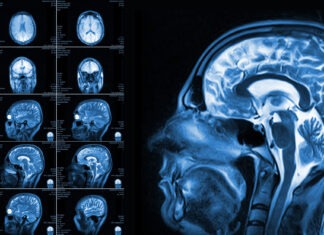

How Do MRIs Work?

Several medical developments have been developed over the years to help in the diagnosis and treatment of diseases. Before, diagnosing diseases were limited because...